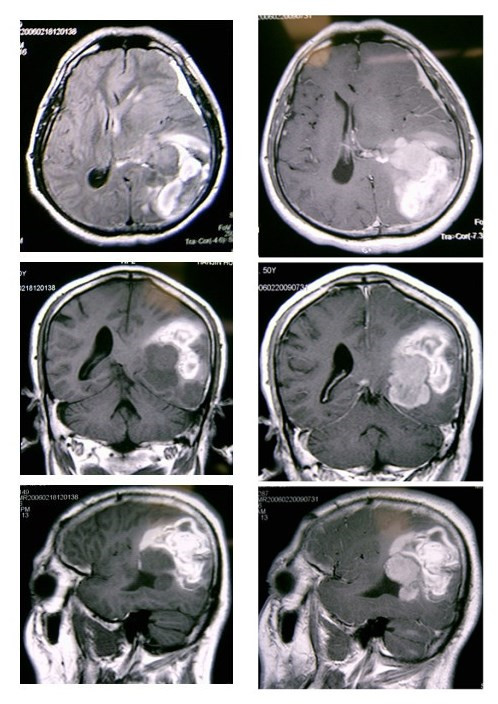

(2)增强扫描时,病灶局部可见增强肿块影,尤其是当非出血区强化则高度提示脑瘤卒中。因此,初次CT怀疑脑瘤卒中时,如果病情允许,建议复查CT及强化CT。MRI显示脑瘤卒中优于CT,若有条件最好做个MRI平扫加强化。见影像片3

影像片3:平扫及强化MRI比较。